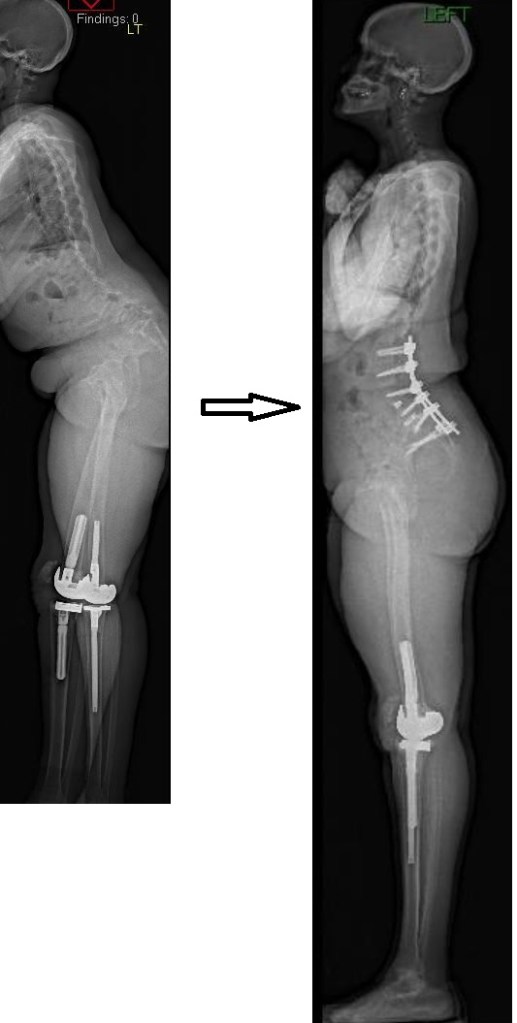

Update on the cervical epidural abscess case: Successful partial C4 corpectomy led to significant neurological recovery. Abscess was more phlegmon than liquid. Used fibular allograft for stability.